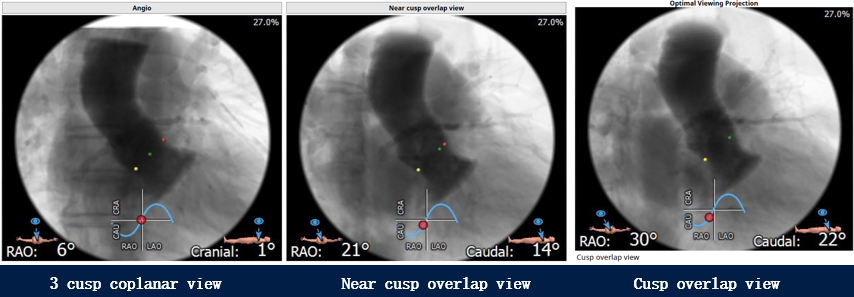

术前明确了常用的工作体位(coplanar view和cusp overlap view)